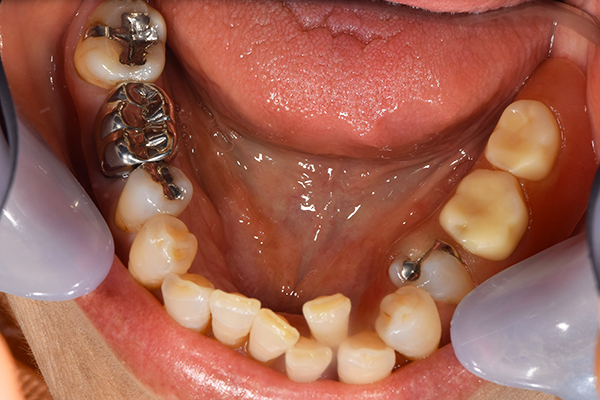

ケース1(自費の部分入れ歯)

前歯が折れて当院にいらっしゃいました。 過去に下の入れ歯を作ったが、合わなくなってずっと入れ歯をいれていらっしゃらない患者様でした。 これは奥歯で噛むことができないため、前歯で噛むことを繰り返したために、負担に耐えられなくなった前歯が折れてかぶせ物ごと 外れてしまったのだと考えられます。 痛くない、違和感の少ない、下の入れ歯を作ることがこの方のゴールであると考えられました。

シリコンで精密な型取りを行いました。

噛み合わせチェックです。 奥歯でしっかりものが噛める様に高さを決めていきました。

金属を使用して、薄く違和感が少ない入れ歯が完成しました。 また、見た目にも気を使い、バネが見えにくい様な構造にしました。

入れ歯をお口の中にいれた状態です。前歯もMTMといって、歯を少し引っ張り出す処置を行なったことで、しっかり残せて、またかぶせ物をしました。

年齢 70歳・女性

主訴 前歯が取れた

治療期間 8ヶ月

治療費 .MTM:110,000円

.ファイバーコア:16,500円

.E-maxクラウン:110,000円

.義歯:660,000円

治療方針 長年使ってきた義歯の人工歯が磨耗し、臼歯部での咬合がすくなくなり、前歯部での接触が強くなったことで生じた前歯の破折なので、義歯も作り変える必要がある。

治療内容 前歯部MTMと同時に審美面の回復。

MTM中に義歯の作成も同時に行う。

最終的に義歯と前歯のクラウンを同時にいれる。

義歯は下顎で、しっかり噛めること、違和感の少ないものという希望があったため、なるべく入れ歯を薄く作成するために金属をしようした義歯とした。

また、見た目もあまり義歯が目立たない様に、バネの部分を見えにくいように作成した。

特記事項 歯にもともと入っていた金属の種類によっては、歯自体の変色を治療で変えられないこともある。 義歯は作ってから痛みがでることがありますが、それは調整を行うことで痛くなくすることができます。